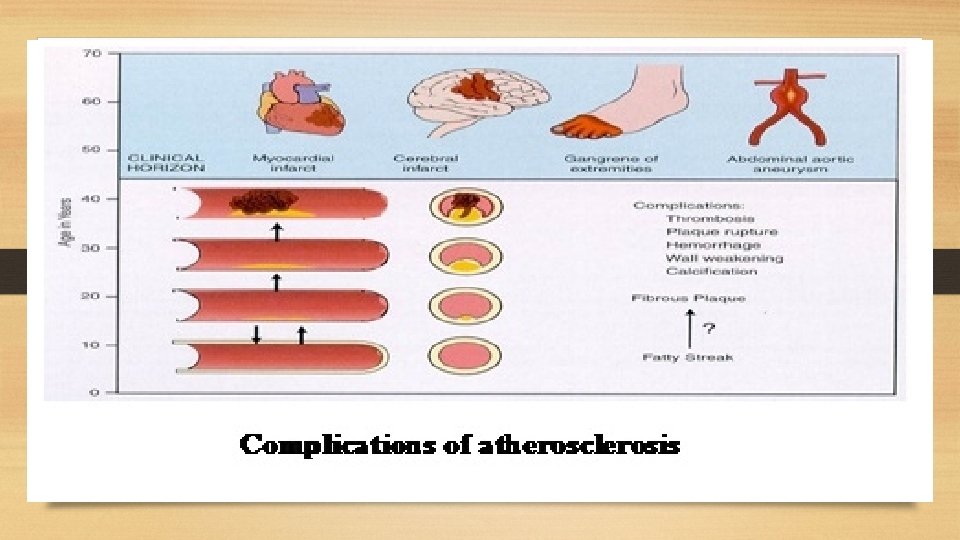

Complications of atherosclerosis: - These account for the most serious harmful effects of atherosclerosis and even death. - It is not uncommon to see more than one form of complication in a plaque. - These changes include: 1. Luminal narrowing: - Causing ischemia or infarction if complete vessel occlusion occurs. 2. Calcification. 3. Ulceration: - The layers covering the soft material of an atheroma may ulcerate. - This results in discharge of emboli composed of lipid material and debris into the blood stream leaving a shallow ulcer with yellow lipid debris in the base of the ulcer. 4. Thrombosis: - The ulcerated plaque and the area of endothelial damage are vulnerable sites formation of superimposed thrombi. 5. Hemorrhage: - Occurs either from the blood in the vascular lumen through an ulcerated plaque or from rupture of thin walled capillaries that vascularize the atheroma. 6. Aneurysm formation: - Due to atrophy, thinning and fragmentation of the internal elastic lamina.